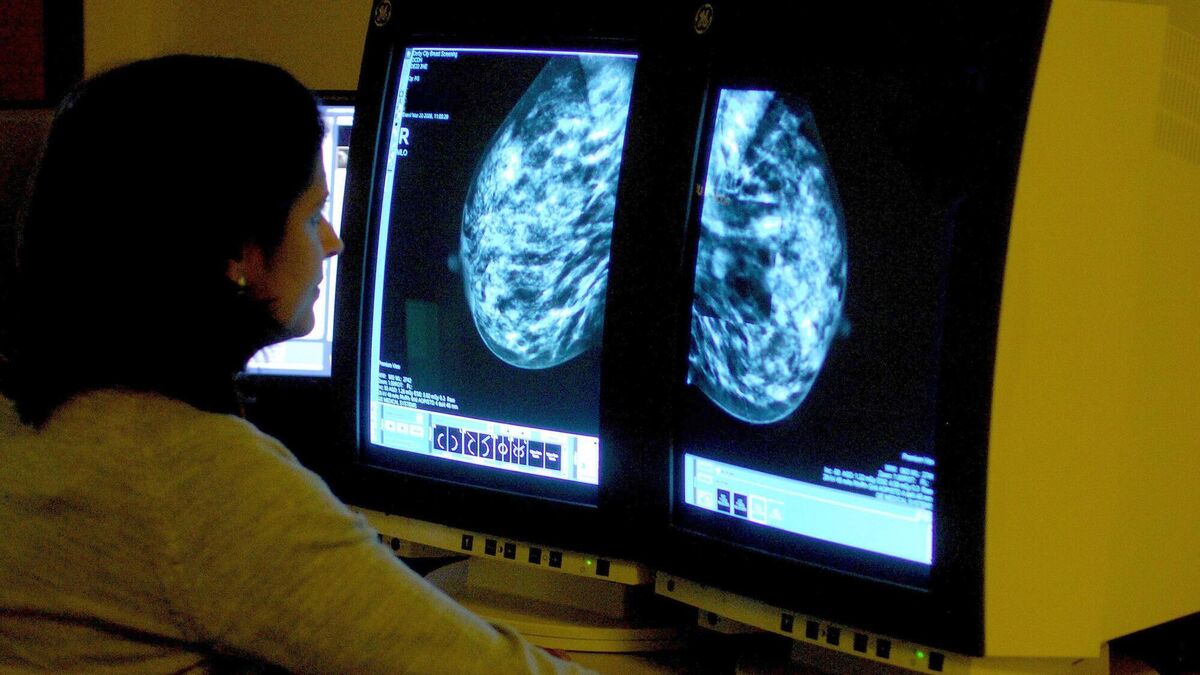

AI is able to improve breast cancer outcomes for patients as the technology can find more early signs of cancer faster than “imperfect” traditional methods.

Artificial intelligence is set to transform Ireland’s breast cancer care, with studies showing it is helping to detect up to 30% more breast cancer cases.

“For decades, mammography has been the cornerstone of early breast cancer detection. It’s a powerful tool, but it’s not perfect.

“Some cancers can be challenging to spot on a mammogram, especially in patients with dense breast tissue.

“With increasing demand for screening, many countries, including Ireland, have a shortage of breast radiologists – the highly-trained doctors who read mammograms.